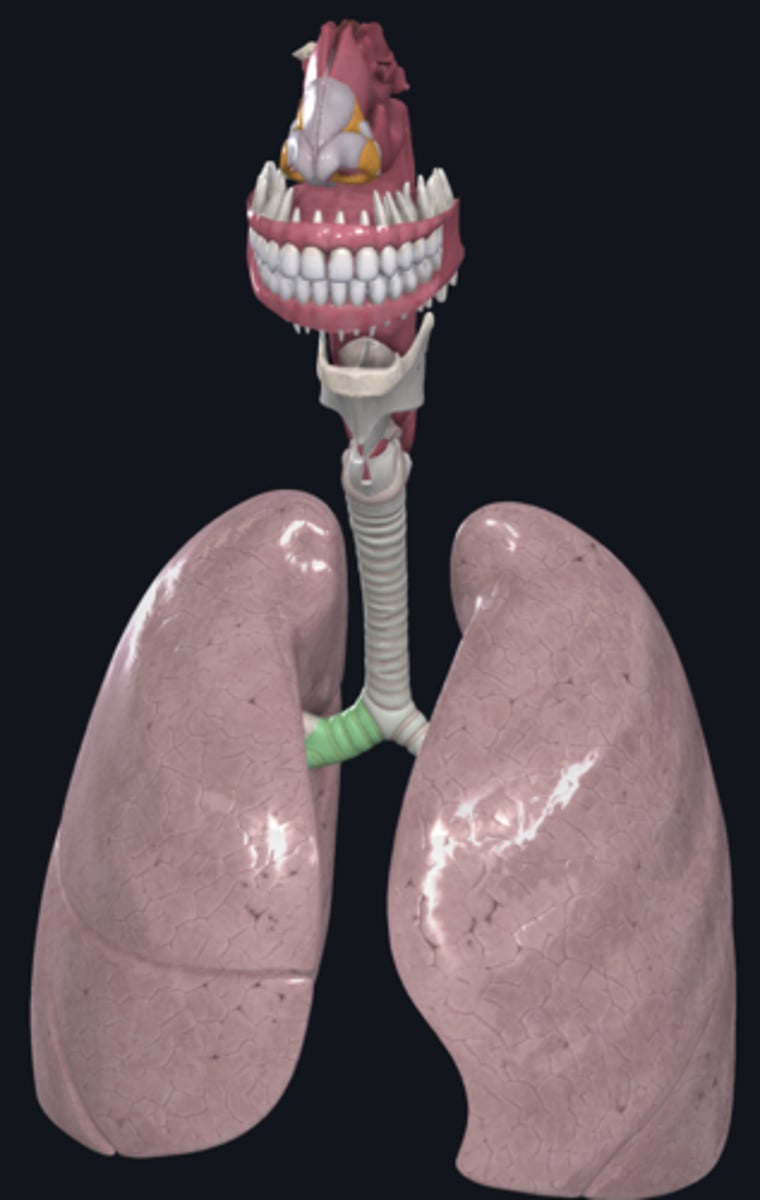

trachea

tracheal cartilage

right lung

left lung

nose

external nares

larynx

hyoid bone

thyroid cartilage

cricoid cartilage

trachea

tracheal cartilages

annular ligament

right main bronchus

left main bronchus